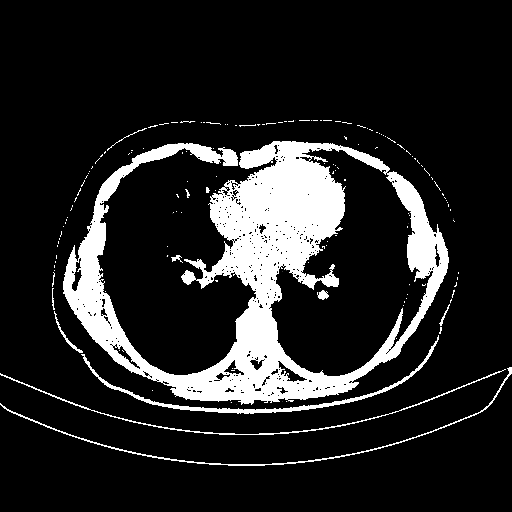

Slice 70 Targeting Evaluation

Patient ID: BM26032018

Model: cytran

Slice: Slice_70

Slice Thickness: 2.0mm

Conversion: NATIVE β VENOUS

4Γ3 grid: Rows show different image types (Original NATIVE, Reconstructed NATIVE, Original VENOUS, Generated VENOUS), Columns show windowing techniques (No Window, Lung Window, Mediastinum Window)